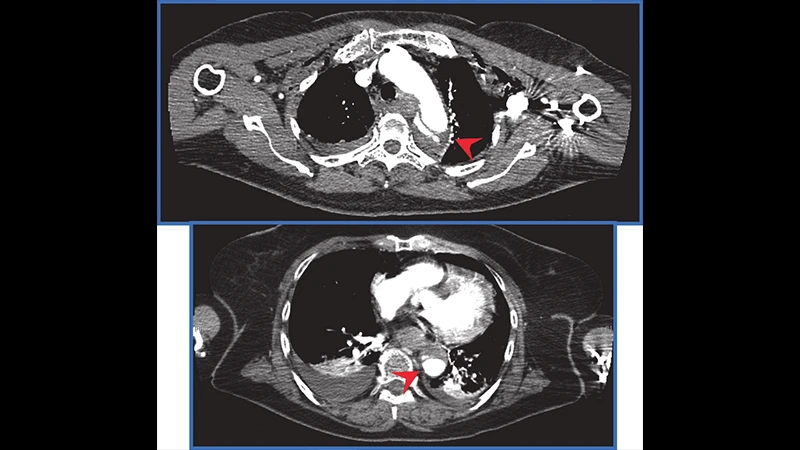

• Chest CT: Provides a much more detailed view than an X-ray, able to detect subtle lung contusions, small pneumothoraces, and injuries to the aorta and other major vessels.

• Abdomen/Pelvis CT: The most important part for identifying internal injuries. It can show lacerations to solid organs like the liver, spleen, and kidneys, as well as signs of active bleeding ("contrast extravasation").

A montage of CT images from a trauma pan-scan, showing slices from the head, chest, and abdomen.